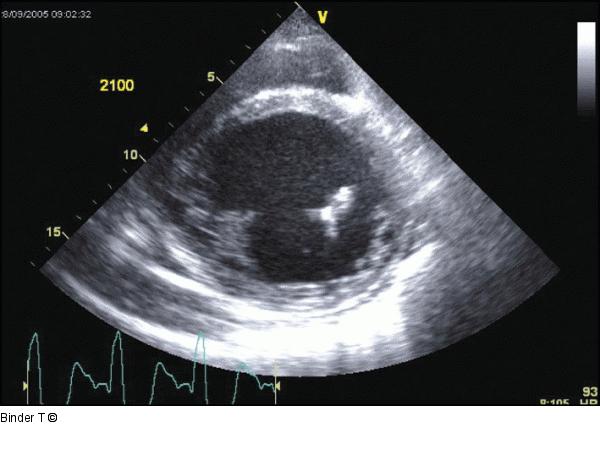

Abbildung 2: Parasternale kurze Achse Dilatierter linker Ventrikel mit höhergradig reduzierter Linksventrikelfunktion. Deutlich asynchroner Kontraktionsablauf mit biphasischer Septumbewegung (mit rascher frühsystolischer Einwärtsbewegung des Septums). Keine regionale Wandbewegungsstörung (spricht für dilatative CMP). Kleiner Perikarderguss hinter dem linken Ventrikel. |

Abbildung 2: Parasternale kurze Achse

Dilatierter linker Ventrikel mit höhergradig reduzierter Linksventrikelfunktion. Deutlich asynchroner Kontraktionsablauf mit biphasischer Septumbewegung (mit rascher frühsystolischer Einwärtsbewegung des Septums). Keine regionale Wandbewegungsstörung (spricht für dilatative CMP). Kleiner Perikarderguss hinter dem linken Ventrikel. |